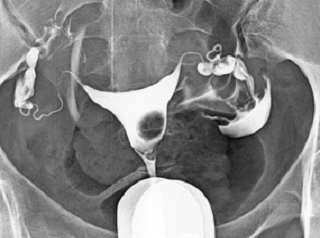

What does HSG assess?

-

Shape of the uterus

Normal shape

Unicornuate uterus

Complete septate uterus

Patency of fallopian tubes

Open tube

Closed tube

Uterine cavity

Clear/Normal

Submucosal fibroid

Adhesions/Synechiae